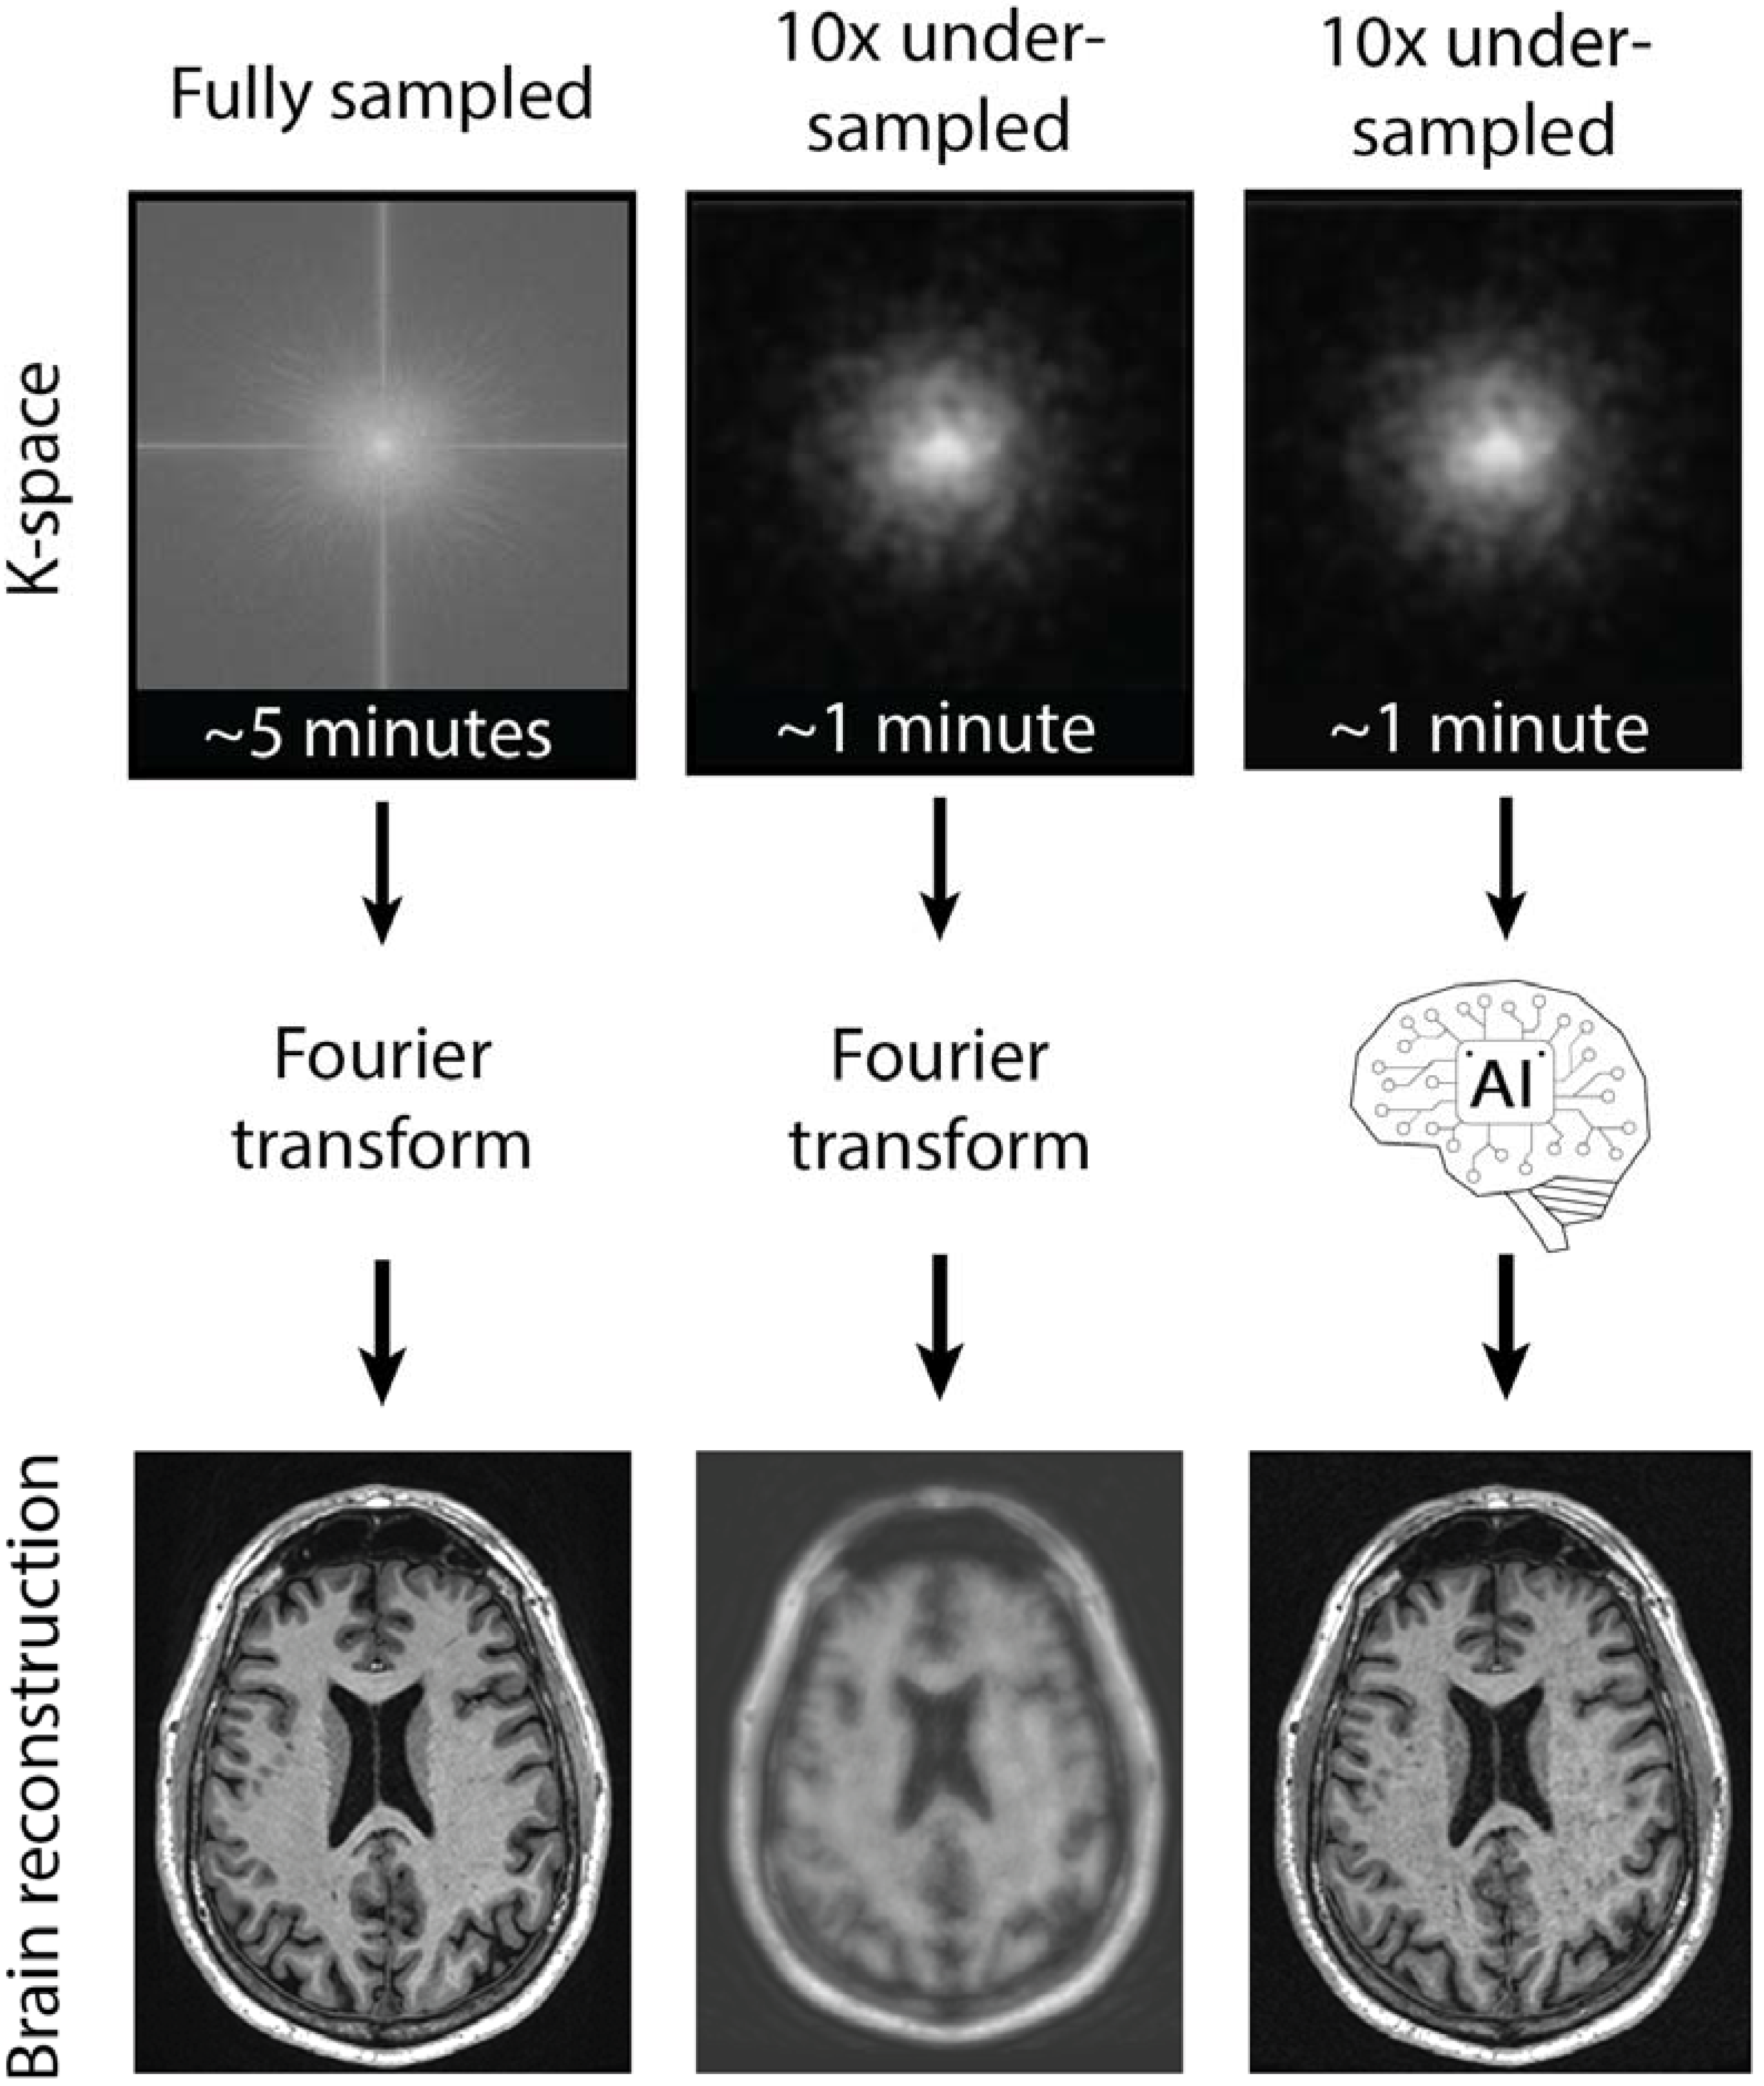

4. AI for Military Medical Imaging